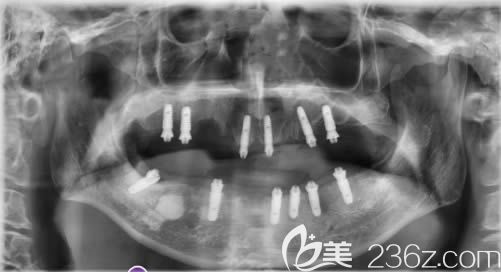

植入口内的12颗种植体:↑↑

我是当天就戴了牙冠,一共植入了12颗奥齿泰种植体,感觉这次种植牙的费用也不算贵。